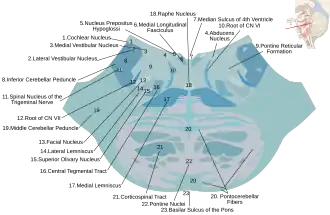

Nuclei

Substanța cenușie este reprezentată de nucleii unor nervi cranieni (motori, senzitivi și vegetativi) și de formațiuni proprii ale punții. În partea dorsală a punții se află nucleii nervilor craniei V, VI, VII și VIII. Nucleul motor al trigemenului este situat în puntea superioară, sub porțiunea laterală a podelei ventriculului IV.[3] Fibrele sale trec ventral și lateral pentru a apărea ca o mică rădăcină motorie la joncțiunea dintre punte și pedunculul cerebelos mijlociu. Lateral de nucleul motor se află nucleul senzorial principal al nervului trigemen. Acesta primește acele fibre ale rădăcinii senzitive care deservesc tactul. Nucleul abducens se află în puntea inferioară, în apropierea liniei mediane, înconjurat fiind de fibre ale nervului facial.[3] Nucleul abducens și fibrele nervului facial formează o mică umflătură, coliculul facial, în podeaua ventriculară. Nucleul facial se situează profund și distal față de linia mediană. O colecție de celule alături de nucleul facial formează nucleul salivator superior (parasimpatic).[3] Din acesta emerg axonii care trec în nervul intermediar al lui Wrisberg și ajung la ganglionii pterigopalatin și submandibular. Partea inferioară formează nucleul salivator inferior, chiar deasupra joncțiunii pontomedulare; fibrele sale se alătură nervului glosofaringian pentru a ajunge la ganglionul otic. Nucleii nervului vestibulocohlear se află sub podeaua unghiului lateral al ventriculului IV (zona vestibulară) atât în punte, cât și în bulb; nucleii vestibulari și cohleari sunt separați. Fibrele vestibulare care emerg din meatul acustic intern trec anterior de pedunculul cerebelos inferior și sinapsează în nucleii vestibulari, multe dintre aceste fibre trecând înapoi în acel peduncul. Alte fibre se alătură fasciculului medial longitudinal și fac sinapsă în nucleii extraoculari și cu neuronii din coarnele măduvei cervicale. Unele dintre aceste conexiuni constituie baza pentru reflexele vestibulo-oculare. Nucleii cohleari sunt în principal bulbari, dar se extind și în puntea inferioară.[3] Aceștia primesc fibre de la ganglionul spiral al cohleei și își trimit axonii în nucleii cohleari dorsal și ventral. Axonii acestora formează corpul trapezoid, parte a căii auditive. Terminațiile cele mai îndepărtate ale nucleului dorsal al vagului și ale nucleului tractului solitar se extind, de asemenea, în punte, dar aparțin în esență bulbului.[3]

Substanța reticulată este situată în partea mijlocie a punții între nucleii nervilor cerebrali și porțiunea bazală, aproape de linia mediană.[1] Ea se compune din fibre și celule nervoase cu așezare dezordonată, formând o substanță care se deosebește atât de substanța albă, cât și de cea cenușie. Micile îngrămădiri de celule nervoase alcătuiesc nucleul reticular în care putem distinge nuclei mai mici.[1] Fibrele au dat naștere aspectului specific și denumirii de substanță reticulată. Parțial, aceste fibre sunt organizate în tracturi motorii ascendente și descendente ca: tractul spinoreticulat, reticulospinal, reticuloreticulat și rubroreticulat.[1]

Locus cœruleus este un grup de neuroni noradrenergici situați în partea superioară a tegmentului pontin dorsolateral. Acești neuroni au axoni extrem de ramificați care se proiectează pe toată suprafața nevraxului și constituie singura sursă de noradrenalină pentru neocortex, hipocamp, cerebel și cea mai mare parte a talamusului.[4] Activitatea neuronală a locus cœruleus joacă un rol central în integrarea informațiilor senzoriale pentru a modula excitarea, atenția și memoria.[5] Aproape de linia mediană de-a lungul nevraxului, dar concentrați mai ales în puntea dorsală, se află nucleii mediani ai rafeului. Acești nuclei conțin neuroni serotoninergici mari care se proiectează extensiv în creier.[6]